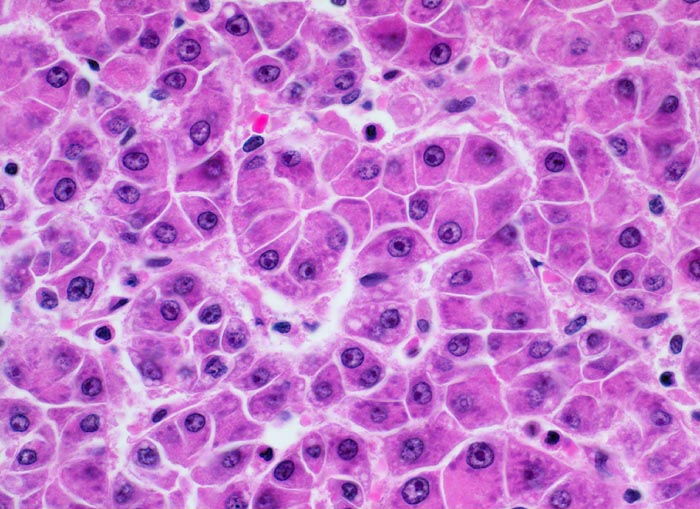

Morphologie: Makroskopisch imponiert das hepatozelluläre Karzinom als solitäre grosse Tumormasse, als zahlreiche zirrhoseartige Knoten oder als scharf begrenzter Knoten mit oder ohne Kapsel. Die tumorfreie Leber ist in der Mehrheit der Fälle zirrhotisch umgebaut. Mikroskopisch bilden die Tumorzellen mehr als 2 Zellen breite Trabekel ( 1237), kompakte Tumormassen ( 1229) oder pseudoglanduläre Strukturen (dilatierte Canaliculi) ( 1212)( 1199). Desmoplastisches Bindegewebe fehlt meist. Innerhalb des Tumors fehlen Portalfelder. Es finden sich lediglich Arterien. Etwa bei der Hälfte der Karzinome lässt sich intrazytoplasmatische oder intracanaliculäre Galle ( 1238) nachweisen. Immunhistochemisch lassen sich mit einem polyklonalen Antikörper gegen Carcinoembryonales Antigen (CEA) Gallecanaliculi zwischen den Tumorzellen nachweisen. Die Tumorzellen bilden keinen Schleim.

Die Tumorzellen bilden Trabekel, welche überwiegend mehr als 2 Zellen breit sind und Pseudodrüsen.

Sinusoidartige Blutgefässe mit Endothelauskleidung verlaufen zwischen den Trabekeln und den Pseudodrüsen.

Die Tumorzellen erinnern an normale Hepatozyten, sind aber kleiner als die Hepatozyten und die Kern-Zytoplasmarelation ist deutlich erhöht. Das Zytoplasma ist basophiler als das der angrenzenden Hepatozyten.

Galle ist sichtbar in den Pseudodrüsen.